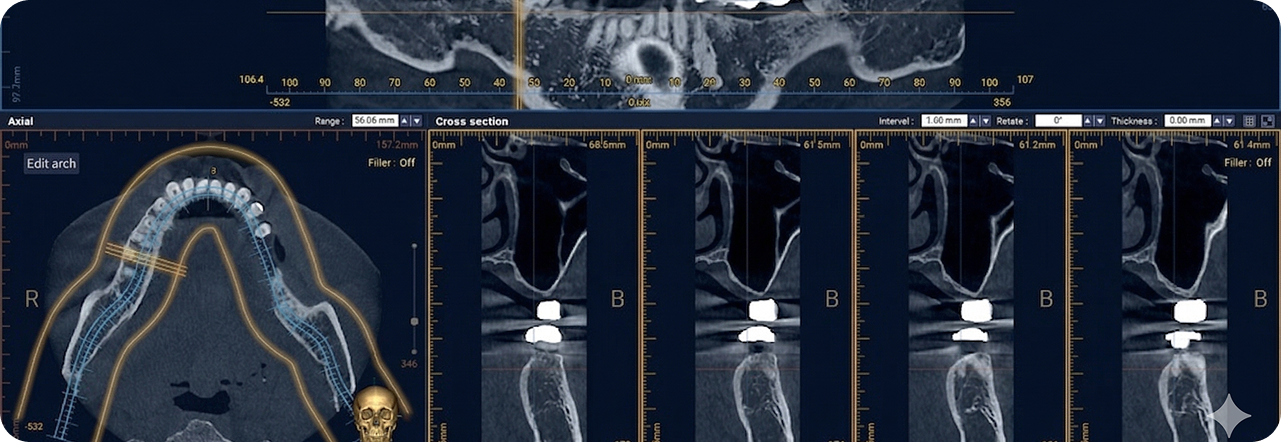

환자의 구강 정보를 디지털 데이터를 기반으로 3D 가상 모의 수술을

진행해 기존 방식 대비 수술 시간이 짧아 체력적 부담을 줄여주고

최소 절개로 통증 및 붓기 최소화로 면역력이 약하거나 회복력이 더딘

고령의 환자, 고혈압 당뇨 등 전신질환을 앓고 계신 분들도 부담없이

안전하게 수술받을 수 있습니다.

성공적인 임플란트 식립을 위해서는 정밀한 진단이 필수적입니다.

3D-CT, 구강 스캐너 등 다양한 디지털 장비를 이용하여

치아, 잇몸뼈, 신경 위치 등을 정확하게 파악해 수술 오차를 최소화하고,

통증 및 출혈을 줄여 더욱 안전하고 편안한 임플란트 식립이 가능합니다.